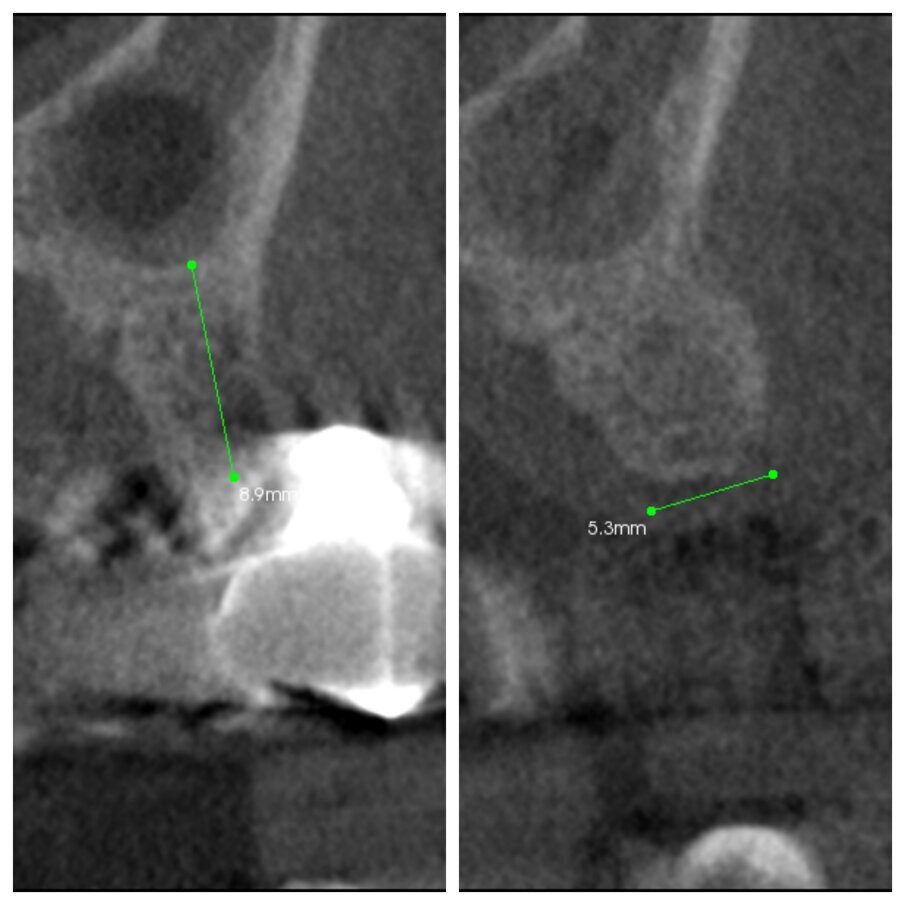

Fig. 2c_CBCT pre e post intervento a 6 mesi.

Fig. 3c_CBCT pre intervento e dopo 6 mesi a confronto.

È oggi molto importante, vista ormai l’evidenza della letteratura scientifica, trattare un alveolo nel momento dell’estrazione e farlo con tecniche mininvasive: biomateriali, membrane in collagene riassorbibile o matrici di collagene esposte in bocca e guarigione per seconda intenzione. Questo tipo di guarigione ci regala un aumento dei tessuti molli cheratinizzati durante la guarigione, al contrario della prima intenzione. Si ha anche un vantaggio estetico poiché la linea muco-gengivale non viene alterata. Può spesso capitarci nella pratica quotidiana di dover estrarre un pilastro di ponte oppure un elemento mesio inclinato, in entrambi questi casi il problema non è l’alveolo da ricostruire ma la cresta guarita a fianco di esso, che quasi sempre presenta un deficit orizzontale più o meno marcato. La tecnica S.A.T (Simplified Apposition Technique), permette di risolvere questo deficit in modo mininvasivo e ricreare un congruo spessore della cresta ossea, fino anche al 50% in più (Figg. 1c, 1d, 2c, 3c), in modo da rendere il sito adatto al successivo posizionamento implantare.

La tecnica semplificata di apposizione del biomateriale (S.A.T.) permette di ripristinare il deficit orizzontale presente a fianco di un dente da estrarre nel modo meno invasivo possibile, facendosi guidare nell’innesto dall’anatomia del sito da ricostruire (Fig. 3c). A distanza di sei mesi i tessuti cheratinizzati sono sempre presenti in ottima quantità (Figg. 1b, 2b, 3b) ed il biomateriale è sempre apparso ben integrato con l’osso nativo sottostante anche senza bisogno di forare la corticale, in questo sicuramente l’alveolo zeppato garantisce un input osteoinduttivo. La stabilità dell’innesto è garantita dalla mancanza di scarichi mesiali o distali, in pratica la busta creata è un sito contenitivo a 4 pareti. Così come risulta fondamentale ricostruire un sito post estrattivo immediato per evitare un collasso dei tessuti duri e molli in senso orizzontale e verticale, è altrettanto importante avere a disposizione una tecnica semplice e poco invasiva per ripristinare contestualmente siti atrofici ereditati da guarigioni precedenti (Figg. 1e, 3e). I risultati avuti finora sono molto buoni e non si sono verificati effetti avversi; ovviamente i numeri dovranno crescere così come i controlli nel tempo (Fig. 6c). Oltre a questo, sarebbe interessante applicare la stessa tecnica di aumento orizzontale dove non vi siano elementi da estrarre ma solo creste guarite con deficit orizzontale, questo amplierebbe considerevolmente le applicazioni di questa tecnica, anche se i risultati mostrati ultimamente dalla tecnica S.M.A.R.T.® incoraggiano nei siti edentuli un approccio laterale.